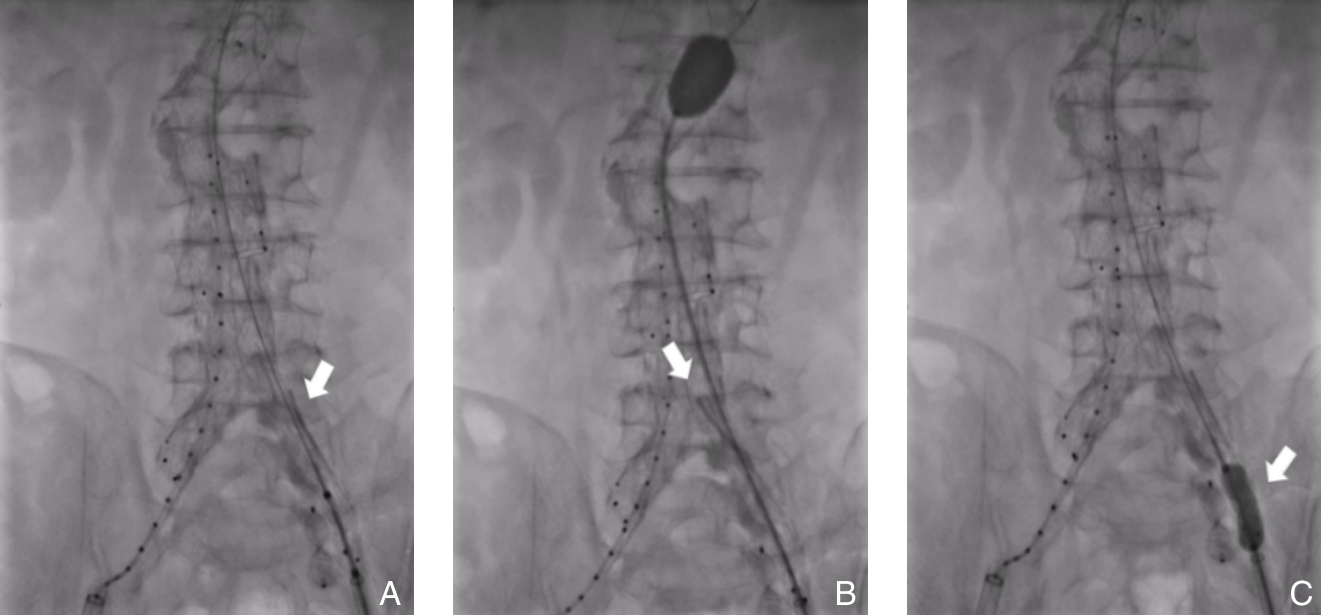

Abdominal aortic aneurysm is a potentially fatal vascular disease commonly encountered in the elderly population. Although endovascular aneurysm repair (EVAR) has become the preferred treatment modality, the incidence of postoperative endoleaks remains high (20%-40%), with more than 30% of cases requiring secondary interventions, thereby significantly compromising long-term outcomes. To standardize the application of fibrin sealant aneurysm sac filling during EVAR, the Vascular Surgery Professional Committee of the Chinese Association of Rehabilitation Medicine convened a multidisciplinary expert panel. In accordance with the RIGHT reporting guideline and the GRADE evidence grading system, and through two rounds of Delphi surveys to prioritize clinical questions combined with systematic evidence review, the committee developed the Expert consensus on fibrin sealant aneurysm sac filling during endovascular abdominal aortic aneurysmal repair. This consensus systematically addresses key aspects including indications and contraindications, technical procedures, dosage estimation, intraoperative assessment criteria, prevention and management of complications, and postoperative follow-up. It defines criteria for complete sac filling and provides tailored application strategies under various anatomical conditions. The aim of this consensus is to standardize clinical practice, reduce the incidence of endoleaks, improve long-term outcomes after EVAR, and provide vascular surgeons with evidence-informed and practically applicable guidance.

-